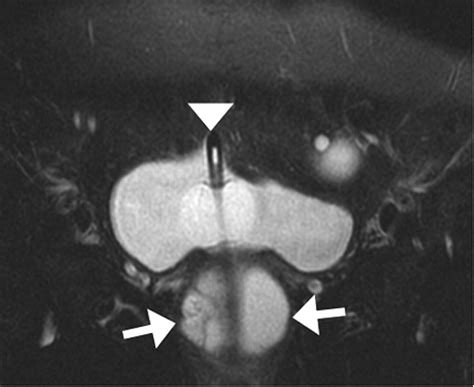

MRI (Magnetic Resonance Imaging) The gold standard for visualizing the size and location of the diverticulum.